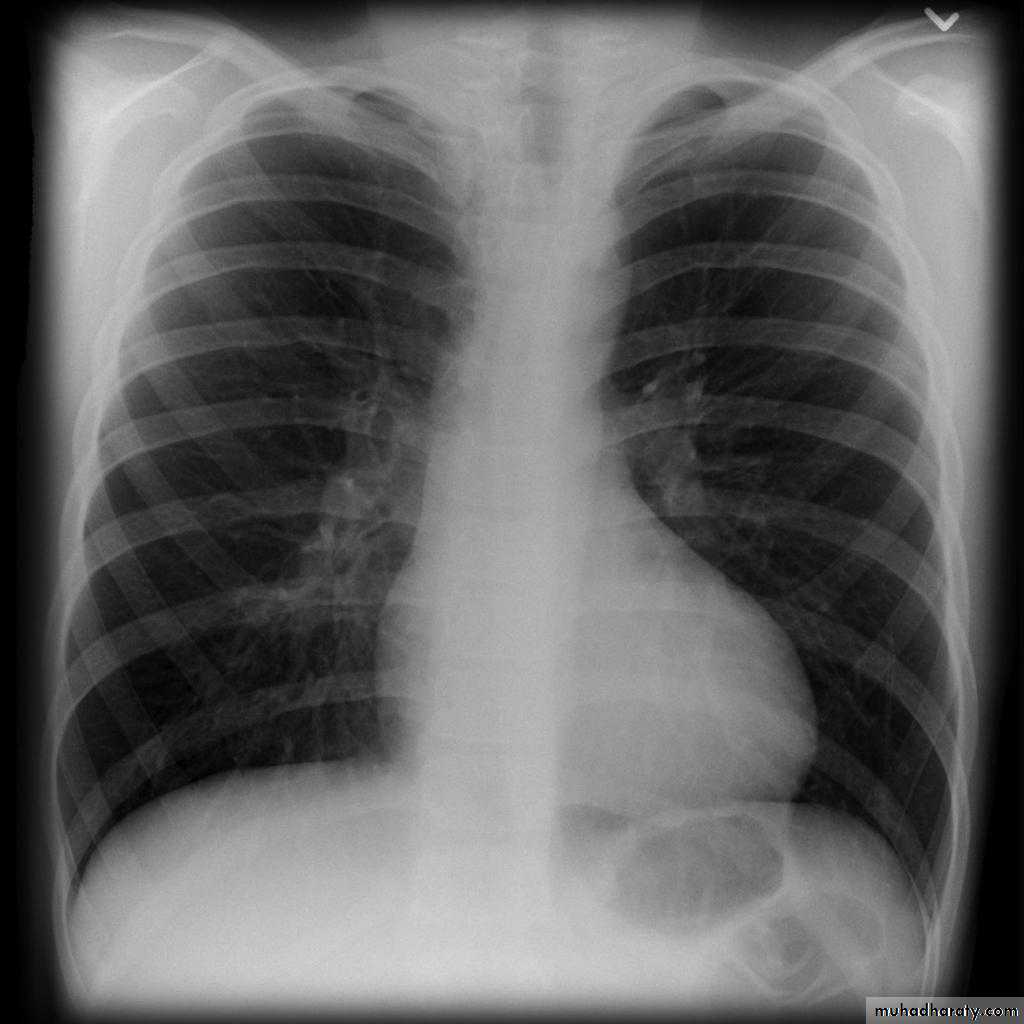

TOF: investigation

ECG:Right ventricular hypertrophy

Chest X ray:

Right ventricular enlargementPulmonary bay (underdeveloped pulmonary artery)

The combination of these findings gives the “boot-shaped heart”